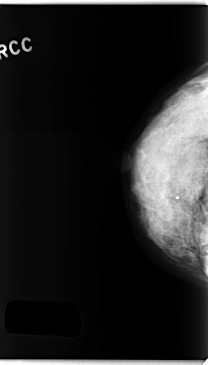

C_0258_1.RIGHT_CC

RIGHT_CC LINES 4736 PIXELS_PER_LINE 2696 BITS_PER_PIXEL 12 RESOLUTION 50 NON_OVERLAY